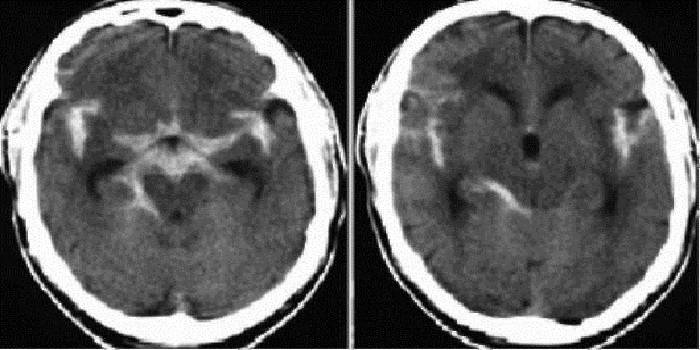

Subarachnoidálne krvácanie z choroby má svoju vlastnú klasifikáciu. Stanovuje sa pomocou základných údajov získaných z CT alebo MRI. Výpočty zahŕňajú masívne krvácanie, kombináciu s parenchymálnym, komorovým krvácaním v lebečnej dutine. Podľa výsledkov diagnózy sa určuje, čo je subarachnoidálne krvácanie: izolované, parenchymálne, komorové alebo parenchymálne-komorové krvácanie.

Potom vykonajte krvný test, aby ste určili zrážanlivosť krvi. Potom sa uskutoční lumbálna punkcia. Za týmto účelom zoberte špeciálnu ihlu a vpichnite do bedrovej oblasti niekoľko milimetrov a extrahujte niekoľko mililitrov mozgovej miechy. Ak je v mozgovomiechovom moku malé množstvo krvi (zrazenín), v subarachnoidálnom priestore sa vyskytlo krvácanie. Na štúdium štruktúry mozgu a zistenie miesta krvácania sa vykonáva počítačová a magnetická rezonancia.

Echoencefalografia môže určiť intrakraniálne subarachnoidálne krvácanie, ktoré môže vytlačiť mozog. Pomocou transkraniálnej dopplerografie môžete vyhodnotiť prietok krvi v mozgových tepnách. Pomôže to zistiť, kde dochádza k vazokonstrikcii. Pomocou angiografie magnetickou rezonanciou môžete vyhodnotiť integritu mozgových tepien, ich vodivosť.

Primárna hospitalizácia pacientov s SAH sa vykonáva v primárnych alebo regionálnych vaskulárnych centrách. Na lôžkových oddeleniach sa pacient podrobuje všetkým procedúram, ktoré pomôžu diagnostikovať ochorenie - MRI mozgu na určenie subarachnoidálneho krvácania (existuje intenzívna biela oblasť) a neinvazívne vyšetrenie cievneho systému (MRI angiografia). Ak sa počas týchto zákrokov zistila neprítomnosť príznakov, je predpísaná bedrová punkcia.